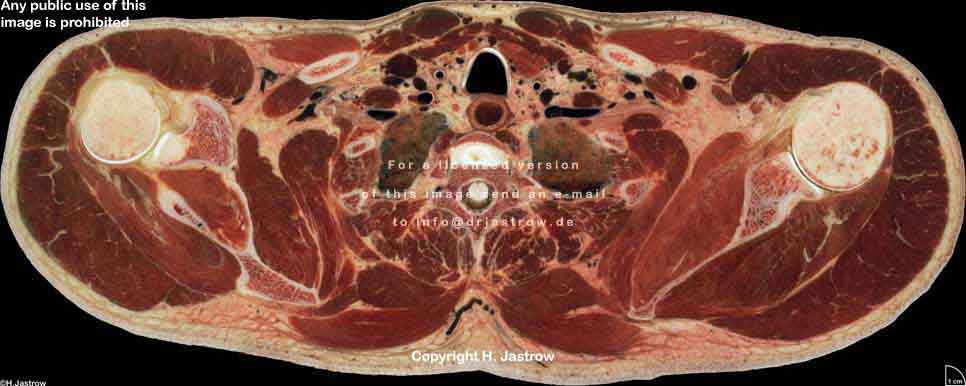

Visible Human male: Sectio transversalis 1305

NMR

Pd T1 T2